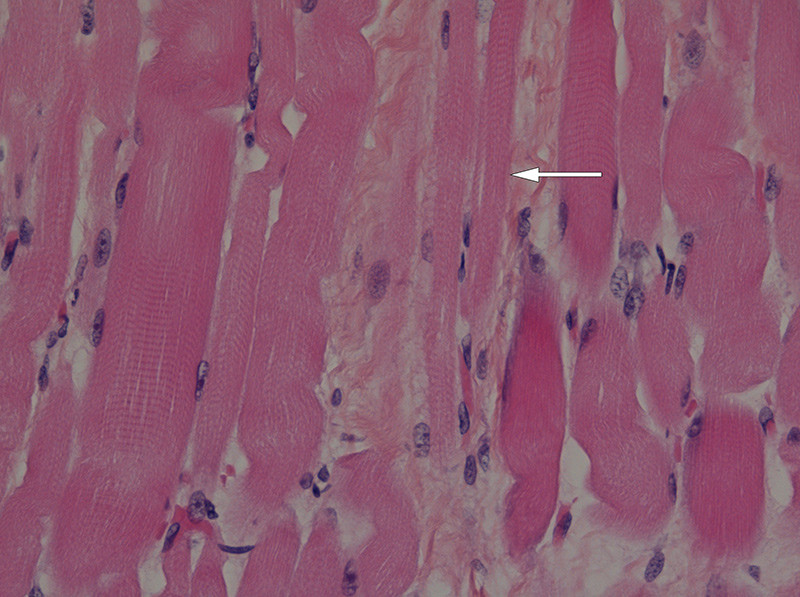

Ved obduksjon ble det funnet tynn diafragma, på kun 1 – 2 mm. Det var svinn av forhornceller i medulla spinalis (fig 1), med usedvanlig små fremre røtter (fig 2). Det var også mulig fibersvinn i kortikospinale baner gjennom hele hjernestammen og i tractus corticospinalis lateralt i medulla. I diafragma fantes spredte grupper av atrofiske fibre og spredte hypertrofiske fibre (fig 3). I skjelettmuskulatur fantes områder med muskelatrofi (fig 4). Det ble fortsatt konkludert med en variant av Werdnig-Hoffmanns sykdom.

De nevropatologiske funn hos disse pasientene varierer. Hos alle finner man muskelatrofi, og mange beskriver forandringer i perifere nerver. Selv om tilstanden oppfattes som spinal muskelatrofi, har ikke alle funnet de forandringer i medullas forhornceller som man ville vente (7). Hos våre pasienter som ble undersøkt, beskrives svinn av nevroner. Både nevropatologiske funn og nevrofysiologiske resultater tyder på perifer aksonal affeksjon og/eller progredierende affeksjon av både motoriske og sensoriske nevroner, der motoriske nevroner blir tidligst og mest affisert.